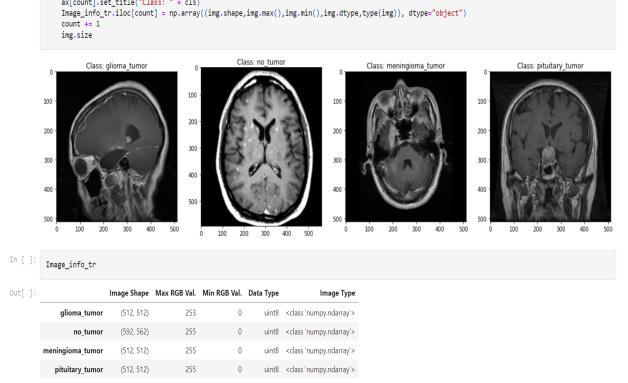

train, test, and partition the data, we will use the Sklearn model.ImageDataGeneratorhasbeenimportedhere.

TrainandValdatasetsareseparatedinthetrainingfolder. Four groups of tumour MRIs are contained in each folder. The epoch rate was set to 50. The dataset file is then unzippedandsavedinapredeterminedpathandfolder.A dictionary is explained in relation to data visualisation. Our four classes ('glioma tumor,' "no tumor," "meningioma," and "pituitary tumor") are the dictionary keys. A directory of images is present in each row. The number of photos in each class in the training and testing sets is then counted using an initialised list. We print the total number of photos in each class for the train and test sets.

Fig.4.5.1.Accuracygraph

Fig.4.5.2.

Predictedclassesoftumor

ResNet is being put into practice in Keras. The dataset for the detection of brain tumours will be used for this implementation. Both the training folder and the testing folderinthisKaggleprojectcontainMRIdata.MRIimages of the corresponding tumour classes are organised into foursubfoldersineachfolder.Webeginbyimportingallof thelibrariesthatarerequiredtoimplementResNet.Given that this is a medical issue and that mistakes can be extremely expensive, we work to create an automated method for identifying and classifying brain tumours. To

Fig.4.5.3.Datasetcount

VisualizeoneimagefromeachclassfortheTrainset,then save the image information in a designated dataframe. Visualize one image from each class for the Test set, then store the image information in a designated dataframe. There are two train and test folders in the Kaggle dataset. In this case, the train set was divided into train and validation sets. Next, we create a straightforward basic model and run MaxPooling. We put up data generators to processModel1'sdatainorderto:Viewtheimagesinour source folders, Feed images to our network along with their labels after converting them to float32 tensors. For thetrainingphotosandthevalidationimages,wewilleach have a separate generator. Our generators will produce batchesof150x150 pixelimagesalongwiththeirlabels.